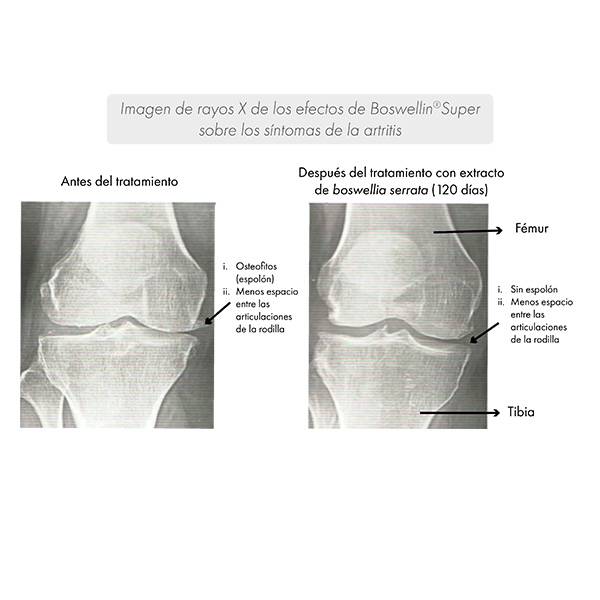

Al mismo tiempo, se demostró una mejoría de los síntomas mediante radiografías.

A los 120 días, se demostró una mejora del espacio interarticular, así como una reducción de los osteocitos.